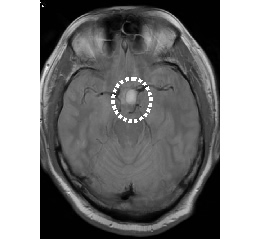

MRI画像

脳腫瘍